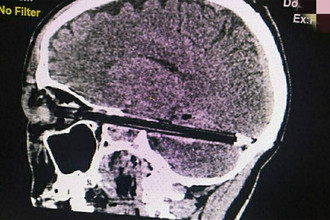

Следователи начали проверку после смерти пациента с шариковой ручкой в голове

Ростовчанин скончался после операции по извлечению ручки из мозга

Врачи спасли ростовчанина с шариковой ручкой в мозгу